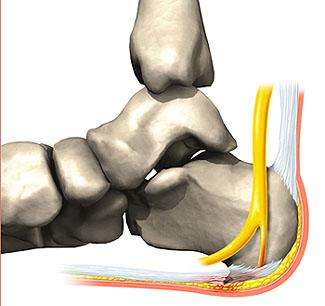

En la porción posterior del calcáneo encontramos estructuras como:

- Bolsa serosa retroaquílea (entre el tendón de Aquiles y el ángulo posterosuperior del calcáneo)

- Cinco bolsas serosas preaquíleas (entre piel y tendón): tres en la línea media y dos laterales

La inflamación de estas bolsas genera dolor en la zona posterior del talón, lo que denominamos talalgia posterior. Es más frecuente en mujeres jóvenes o adolescentes.

Figura 3. Espolón calcáneo posterior

La etiología de estas bursitis retro o preaquíleas se basa en microtraumatismos por compresión, ya sea externa o interna:

- Compresión externa: zapatos con contrafuertes altos, incurvados o inadecuados, tacones excesivos, calzado sin sujeción anterior.

- Compresión interna: deformidad conocida como calcáneo de Haglund (ángulo posterosuperior del calcáneo más puntiagudo).